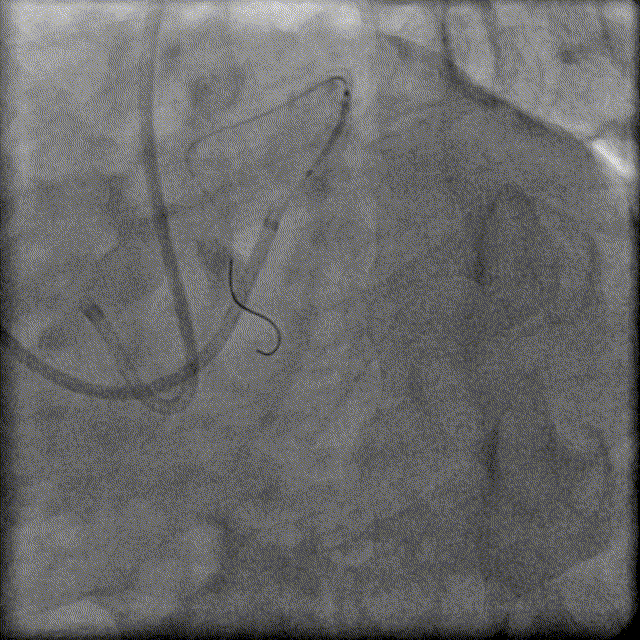

换用Instantpass微导管(170cm)支撑下送Fielder XT-R导丝通过LAD-RCA心外膜侧枝逆向通过RCA闭塞病变,推送微导管后交换Gaia Third导丝,RCA正向送Telescope™导引延长导管进行主动迎接Gaia Third导丝。

于PDA-RCA开口近段病变处植入2.5×30mm、2.75×30mm、3.0×30mm、3.5×22mm Resolute Integrity支架,2.0×15mm Emerge球囊主动拘禁保护PLA。

3.0×15mm、3.5×15mm NC Sprinter球囊以12-16atm×15秒后扩。

IVUS显示支架贴壁良好,未见夹层,RCA中远段MSA 7.41mm²,术毕。